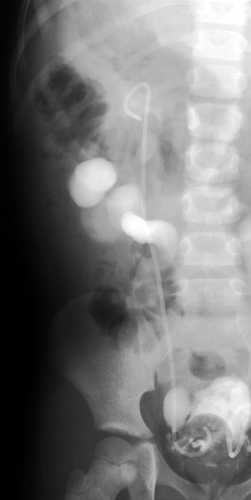

Niña de 8 años con historia de infecciones urinarias de repetición secundarias a un reflujo vesico-ureteral de grado IV.